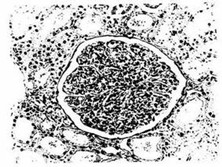

非IgA系膜增生性肾炎是指光镜下病理学改变以弥漫性系膜细胞增生和/或系膜基质增宽的一组疾病。本病多数起病隐匿,部分起病前有感染史,以上呼吸道感染为多,病原不明确。

A: 非IgA系膜增生性肾炎是一种以肾小球系膜细胞增生和基质增多为主要病理特征的肾小...

A: 非iga系膜增生性肾炎是一组疾病。患者表现为系膜增生,如果有系膜增生和iga沉积...